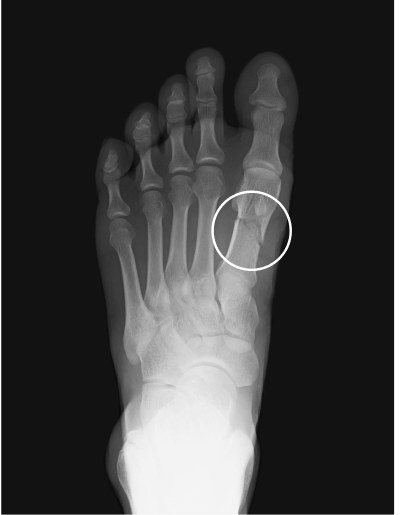

Metatarsal fracture

age 16

Femur fracture

age 13

Tibial fracture

age 57